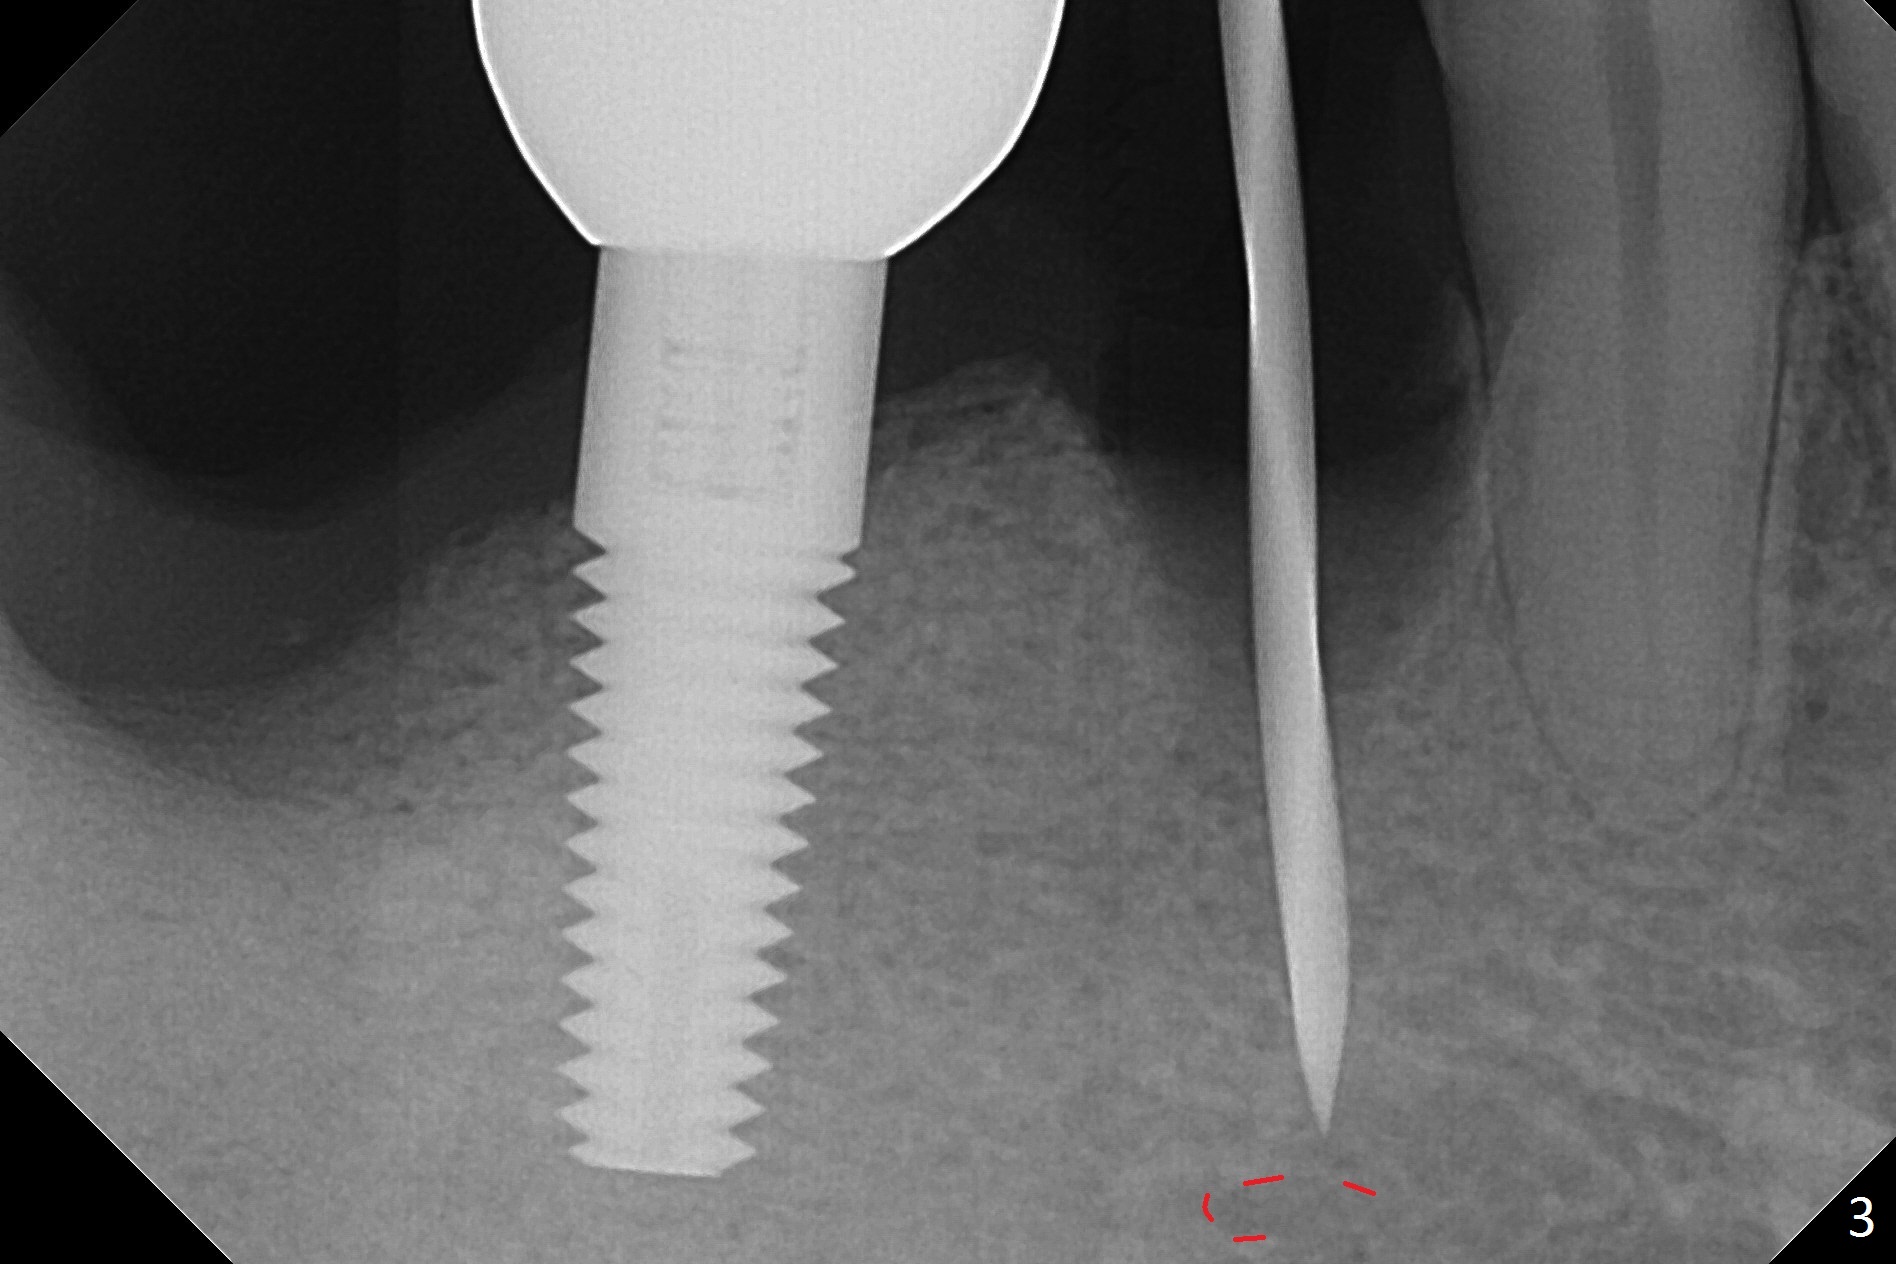

The affected tooth (#28) has buccal gingival recession (Fig.1). As expected, the buccal plate is found low after extraction. Osteotomy is established in the lingual slope of the socket with 1.5 mm drill for 13 mm (Fig.2,3). Following use of Magic Drill 3.3 mm for 13 mm, a 4x11 mm dummy implant is incompletely seated (Fig.4); it is also close to the Mental Loop (Fig.4 red line). After use of Final Drill, a 4x9 mm IBS implant is placed 4 mm and 2 mm subgingival buccal and lingual, respectively (Fig.5) with a large buccal gap (Fig.6 (40 Ncm)). After placement of allograft in the peri-implant space (Fig.7 *), a 4.5x5.7(4) mm abutment is placed (A). A piece of gauze is placed in the remaining buccal space prior to provisional fabrication (Fig.8 *). The space occupied by the gauze is later filled with collagen plug before provisional seating. The gingiva is healthy around the provisional 12 days postop (Fig.9). To reduce buccal gingival recession, the buccal margin of the provisional is shortened 4.5 months postop (Fig.10 arrow). PA taken 5.5 months postop is shown with the implant at 31. The lingual gingiva is erythematous, edematous, and recessive with +BOP and deep pockets 14 months postop (Fig.11). It appears that the small and short implant is not favorable for healing. The infected implant is removed with the missing buccal plate; bone graft is placed 15 months postop (7 months post cementation, Fig.12,13).